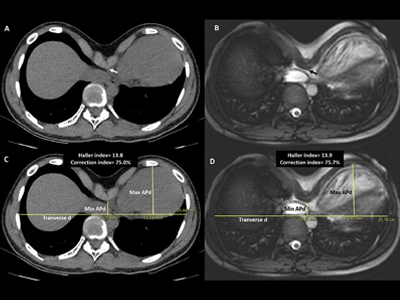

Objetivo: la evaluación preoperatoria de pacientes con pectus excavatum (PE) exige la evaluación de la malformación índices, generalmente con tomografía computarizada (TC) de tórax. Además, la evaluación del impacto cardíaco de La depresión esternal se ha convertido en una regla en los centros de alta referencia, por lo que se requieren dos modalidades de imágenes independientes y utilizar radiaciones ionizantes en una población muy joven. El objetivo de este estudio fue explorar el acuerdo entre la TC de tórax y la RM cardíaca estándar (RMC) para la evaluación de los índices de malformación de la pared torácica.